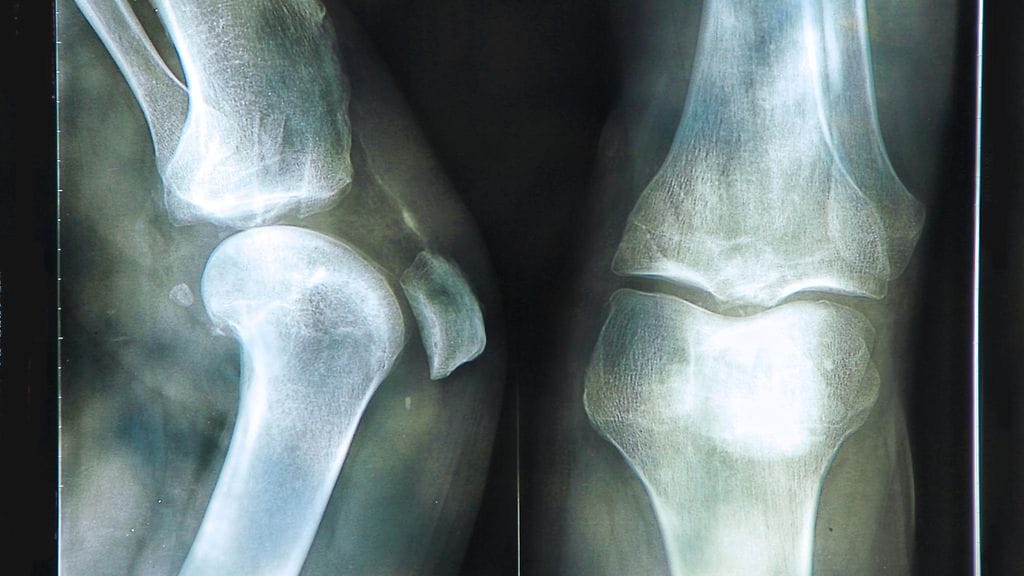

Keliakiaa sairastaa arvioiden mukaan kaksi henkilöä sadasta ja se aiheuttaa puutteellista ravintoaineiden, kuten kalsiumin ja D-vitamiinin, imeytymistä. Niinpä keliakiaa sairastavilla on kohonnut riski sairastua osteoporoosiin.

Keliakia olisi tärkeää löytää sekä aloittaa gluteeniton ruokavalio mahdollisimman pian sen ensimmäisten oireiden ilmaannuttua. Hoitamattomana keliakia voi johtaa osteoporoosiin. Gluteeniton ruokavalio on tällä hetkellä keliakian ainoa ja koko eliniän kestävä hoitomuoto.